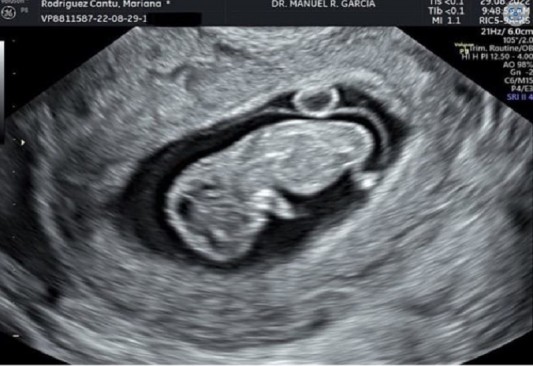

¡Bebé en camino! Mariana Rodriguez y Samuel García anuncian embarazo

El gobernador de Nuevo León, Samuel García Sepulveda, y su esposa Mariana Rodríguez anunciaron que esperan a su primer bebé.

Baby on the way! Estamos felices de compartirles que pronto seremos 3. Tanto tiempo hemos esperado este momento y no lo podemos creer que ya esté con nosotros un/a bebesit@. En estos dos años y medio hemos aprendido que los tiempos de Dios son perfectos, ni un día menos, ni un día más, escribió la titular de AMAR a Nuevo León.

El gobernador de Nuevo León compartió la publicación también en su página personal en la que escribió: Pronto seremos 3. Te esperamos con ansias.